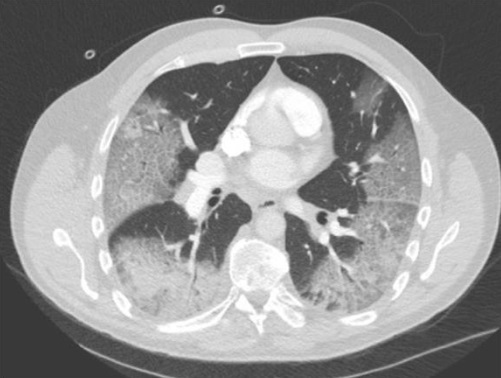

¿Cuál es el dx?

Neumotórax